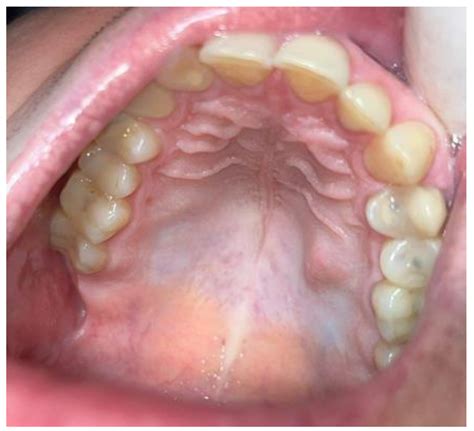

A swollen mouth palate, or oral mucosal swelling, occurs when the soft tissue on the roof of the mouth becomes inflamed and enlarged. This condition can affect anyone, regardless of age, and can be caused by a multitude of factors. The palate is a crucial part of the oral cavity, playing a significant role in speech, swallowing, and breathing. When it becomes swollen, it can disrupt these functions and cause discomfort.

Special Considerations for Children

Children are particularly susceptible to oral mucosal swelling due to their developing immune systems and frequent exposure to infections. Parents should be aware of the following considerations:

• Children may be more likely to experience allergic reactions to foods or medications.

• Dental issues, such as cavities or impacted teeth, can cause swelling.

• Children may be more prone to injuries from falls or accidents.